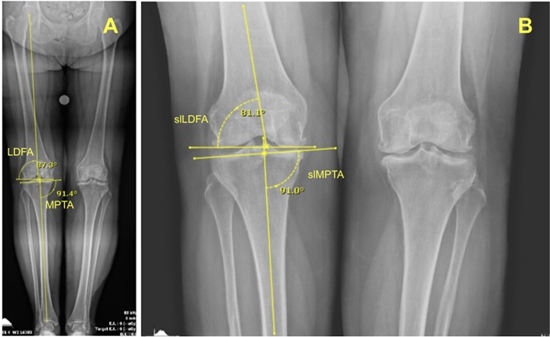

Preoperative SLRs and LLRs were utilized for measurement. Two independent raters reviewed all patients’ short- and long-leg AP weight-bearing radiographs to assess knee alignment. Long-leg radiographic measurements included the lateral distal femoral angle (LDFA) and the medial proximal tibial angle (MPTA). From these, the arithmetic hip-knee-ankle angle (aHKA) was calculated as MPTA minus LDFA, and the joint line obliquity (JLO) was calculated as the sum of LDFA and MPTA. For short-leg radiographs, measurements included the short-leg LDFA (slLDFA) and short-leg MPTA (slMPTA). Corresponding calculations included the short-leg arithmetic HKA (slaHKA), defined as slMPTA minus slLDFA, and the short-leg JLO (slJLO), defined as the sum of slLDFA and slMPTA. Long-leg radiographic measurements were obtained following the methodology described by Graden et al and others [2,13-15]. For SLRs, in cases where the hip and ankle were not visualized, lines were drawn through the center of the femoral and tibial diaphysis (Figure 1).

Figure 1: Long-leg (A) and short-leg (B) radiographs of a knee showing the lateral distal femoral angle (LDFA) and the medial proximal tibial angle (MPTA) measurements to determine Coronal Plane Alignment of the Knee (CPAK) classifications.